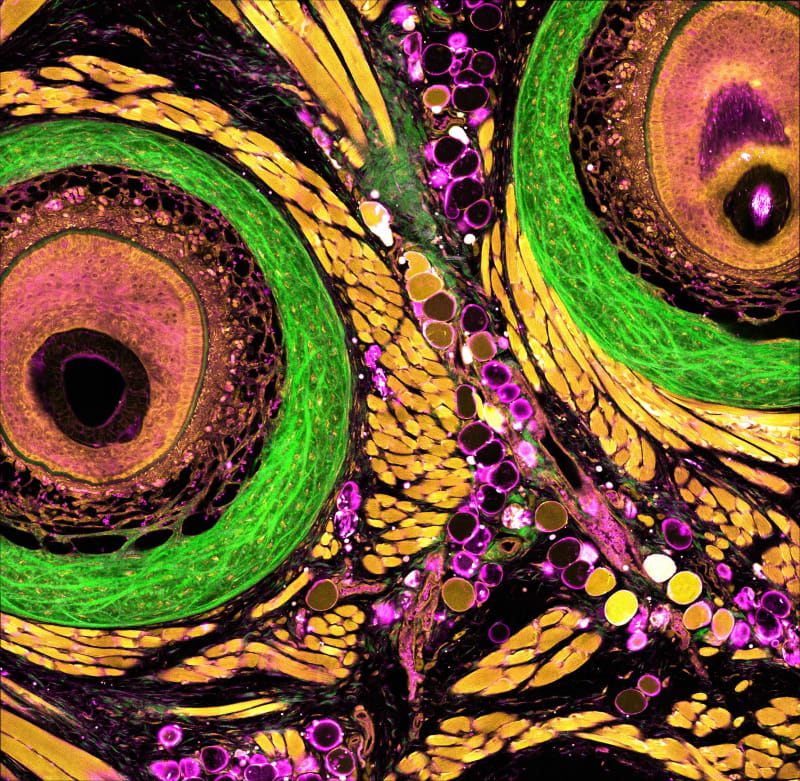

Our team has created a new powerful imaging platform called dSLAM (deep and dynamic simultaneous label-free imaging of autofluorescence and multiharmonic). This system enables researchers to visualize live, intact tissues in action-without the need for any fluorescent dyes or genetic labels, with intrinsic metabolic and structural contrast, at three times deeper depth than existing label-free imaging platforms. Label-free imaging uses the cells' natural glow, known as autofluorescence, to monitor metabolic activity in a completely noninvasive way. While this concept has long held promise, traditional approaches have struggled with poor resolution, limited imaging depth, and slow data collection. We addressed these challenges with a set of novel innovations:

- Sharper, deeper label-free imaging: By using a three-photon NADH excitation, we significantly reduce how much light scatters inside tissue. As a result, we can now capture clear metabolic images more than 700 microns below the tissue surface-over twice the depth possible with older technologies-without sacrificing resolution.

- AI-powered clarity: We also developed an artificial intelligence tool called SSAI-3D, a self-supervised software system that removes blur from deep tissue images. This approach works across various microscope types and sample conditions, and it doesn't require any special hardware or labeled training data. With SSAI-3D, we recover full 3D resolution-around 500 nanometers in the three xyz dimensions-even in thick, complex tissue.

Together, these technologies make it possible to observe the structural and metabolic changes of living systems with unmatched depth, speed, and precision. Importantly, the platform is adaptable across different types of samples and imaging setups.

We've already used dSLAM to solve pressing biomedical problems. In collaboration with MIT's Prof. Roger Kamm, we imaged a full 700-micron depth of a human blood-brain barrier model, helping to visualize how therapeutic drugs may (or may not) pass into the brain. In a separate project with MIT’s Prof. Linda Griffith, we captured dynamic changes in human endometrial tissue across the menstrual cycle. This research is opening new doors in understanding hormone response, treatment effects, and patient-specific differences in reproductive health.